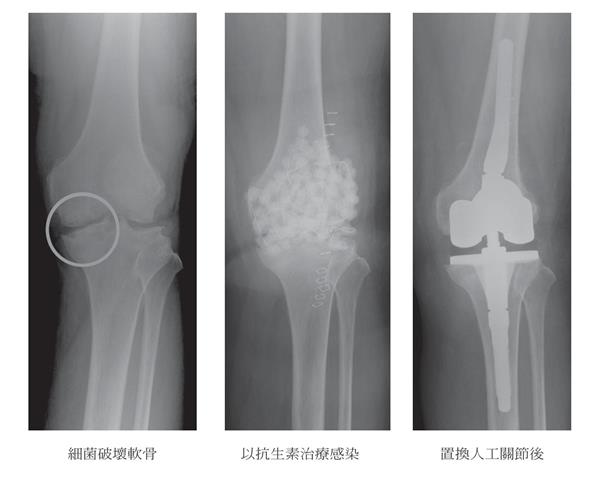

前來我們關節中心尋求進一步治療的慢性膝痛病患,經仔細詢問,十之八九曾接受過關節腔注射透明質酸的療程,評價好壞參半(與安慰劑差不多),以其高成本來看,若只能得到短暫的安慰劑療效,確實應三思而行!若使用不當(未順利注入關節腔)或關節滑液囊對透明質酸產生過敏發炎反應,反而使疼痛加劇,甚至導致關節滑液囊因重複發炎而逐漸變厚、失去彈性,偶而也會碰到因侵入性細菌感染而必須接受重複清創手術、提早置換人工關節的病例,得不償失!

▲重複注射玻尿酸,導致細菌感染,軟骨嚴重受損,只能以人工關節置換手術挽回功能